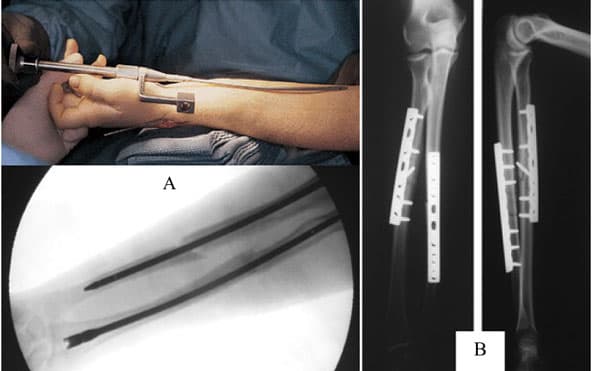

Kết hợp xương bằng nẹp vít được áp dụng trong các phẫu thuật xương khớp. Nẹp ở vị trí trước trên (trên mặt căng của xương) tạo ra sự vững chắc sinh cơ học hơn ở những nơi khác, tuy nhiên đặt nẹp ở vị trí trước dưới cũng thành công về mặt lâm sàng. Các thuận lợi khi đặt nẹp trước dưới là ít có khả năng gây tổn thương phổi, màng phổi, bó mạch dưới đòn khi bắt vít và về lý thuyết cách đặt nẹp này ít gây ra sự kích thích với implant. Đặt nẹp ở vị trí trước dưới cũng có một số bất tiện. Đó là cần phải bóc tách thêm mô mềm và khó tạo hình nẹp hơn, dù nẹp tạo hình trước cho từng vị trí gãy đã có sẵn.

Ngoài ra, việc kết hợp xương còn dùng các loại đinh nội tủy, kim Kirschner, dây thép làm giá đỡ kim loại bất động phần xương bị gãy giúp cơ thể tự hồi phục liền xương.

Không những kết hợp được xương dài, phương pháp kết hợp xương bằng nẹp vít còn có thể cố định hoặc thay thế khi bị gãy, vỡ, mất xương ở xương bản rộng như xương sọ, xương bả vai, xương chậu mà không có cách bó nào làm được, đặc biệt quan trọng như thay thế mảnh khuyết xương sọ bằng mảnh ghép bằng titan.